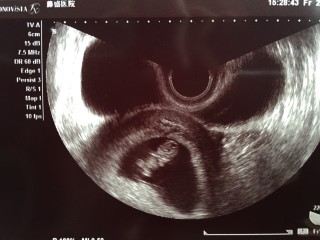

初診から2週間後の9週目。 大きさ22.4㎜。 ただの丸い形から一気に人間らしくなっててびっくり!元気に動いてたので、写真がブレブレ。その中からのベストショット。かわいいな。

初めて心音を聞きました。すごい速さで力強く動いててびっくり★CRLは22ミリでした。 出血があったりしたので不安でしたが、安心しました^^ 元気に育ってね!